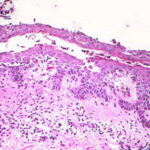

Histopathology. The earliest change consists of acantholysis in the upper epidermis, within or adjacent to the granular layer, leading to a subcorneal bulla in some instances . More commonly, enlargement of the cleft leads to detachment |

of the stratum corneum without bulla being seen. The number of acantholytic keratinocytes is usually small, often requiring a careful search to identify them. Secondary clefts may develop, leading to detachment of the epidermis in its mid level. These clefts may extend to above the basal layer, rarely giving rise to limited areas of suprabasal separation. In the setting of a subcomeal blister, dyskeratotic granular keratinocytes are diagnostic for this disorder. Eosinophilic spongiosis may be prominent with intraepidermal eosinophilic pustules. Thus, the histologic features of pemphigus foliaceus may have three pattems: {a} eosinophilic spongiosis; {b} a subcorneal blister, often with few acantholytic keratinocytes; and {c} a subcorneal blister with dyskeratotic granular keratinocytes , diagnostic of this disorder. The character of the inflammatory infiltrate is variable and depends on the age of the lesion, whether a blister is present, whether the superficial portion of the epidermis has been detached, and whether there is impetiginization or necrosis of the blister roof. |